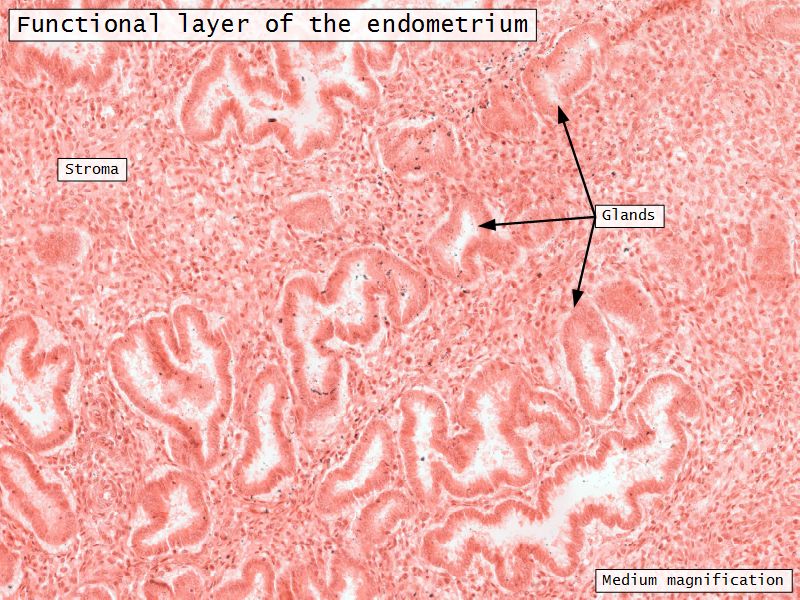

- Functional layer

Functional layer

- Thick superficial layer

- Cyclic monthly hormonal changes

Endometrial glands

- Extend through basal layer

- Source of cells to reestablish endometrium

Blood supply

- Originate from myometrium

- Helical arteries

- Extend into functional layer

- Straight arteries

- Terminate basal layer

Menstrual cycle

- Follicular phase

- Luteal phase

- Menstrual phase

Follicular phase

- Epithelium reform

- Proliferation of

- Glands

- Connective tissue

- Blood vessels

- Glands become coiled

- Helical arteries 2/3 into endometrium